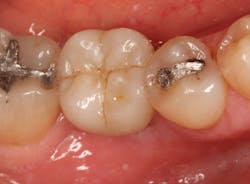

JC is a 57-year-old female with a retained primary tooth K and a congenitally missing No. 20. K was becoming increasingly mobile and developed bone loss beyond the apex of the distal root, necessitating removal of the tooth.

Excellent interseptal bone width was present, both buccal and lingual plates were present, and an adequate amount of bone was present coronal to the inferior alveolar nerve to allow for immediate implant placement. A sulcular incision was made around K and the adjacent teeth, and a full-thickness buccal and lingual flap was reflected. The tooth was sectioned in half, and the mesial and distal roots were elevated. The socket was degranulated with a round diamond bur and copiously irrigated with chlorhexidine gluconate 0.12% rinse. An osteotomy was completed in the interseptal area, and a bone-level 4.8- x 10-mm implant was placed to 35 Ncm. A mixture of cancellous and cortical allograft was infused with autogenous plasma-rich growth factor (PRGF), which was isolated during a preprocedural blood draw. The mixture was packed into the residual socket, slightly coronal to the implant platform to account for predictable resorption during healing. (13)